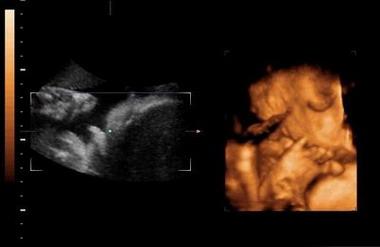

四维彩超一般准确率是超过80%的,但是由于很多的因素,也会发生检查结果翻盘的情况,四维彩超其实是实时的三维,是有一个立体成像的过程,因为胎儿是团抱式的,胎儿一部分会被遮挡,所以四维应该会更准确一些,但是不是绝对的。实际在B超进行胎儿性别鉴定时,有可能男孩生殖器被遮挡导致误认为是女孩,也可能把女孩的脐带当成生殖器误认为男孩。

当医生正在操作B超的时分,若宝宝正处于背部的姿态或手脚正好蜷到一同,从而遮挡了性别器官,这也会形成性别的改动,另外假如你家宝宝太调皮了,不太配合,姿态不对,医生也不可以很精确的看到Ta的生殖器,结果就没有那么精确了。

四:通过四维彩超图看清胎儿性别,在六个月以后照四维彩超,只要宝宝的姿势是正面不是给个背影什么的,是男是女一看就知道。不过因为国家明文规定不能查胎儿性别,所以医生不会把能明显看出性别的一面照给妈妈看。